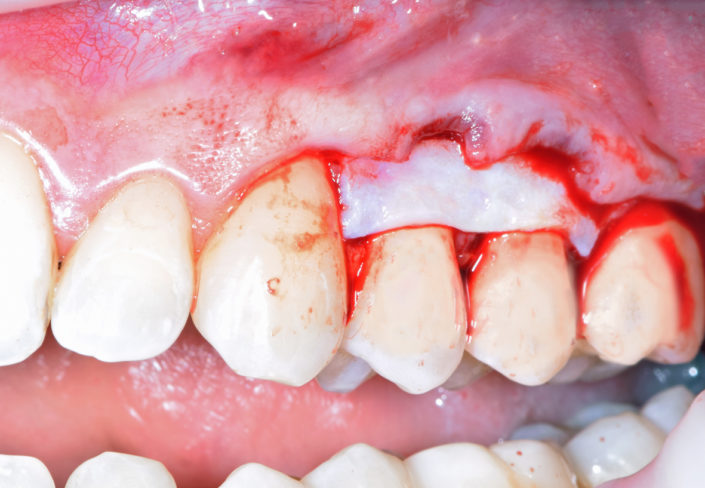

La patiente a été adressée au cabinet par son dentiste traitant pour une solution de remplacement de son bridge maxillaire en fin de vie. Une solution implantaire lui a été proposée pour la réhabilitation de sa mâchoire soit les extractions des dents, mise en place des implants avec aménagement osseux, le tout lors de la même intervention sous sédation vigile. Un Bridge fixe implantaire provisoire et esthétique a été placé 48 heures après l’intervention. Cette prothèse restera en bouche au moins 6 mois pour valider les implants, l’esthétique et la fonction avant de passer aux empreintes pour la prothèse finale (bridge céramique) qui sera totalement adaptée et personnalisée à la demande de la patiente.